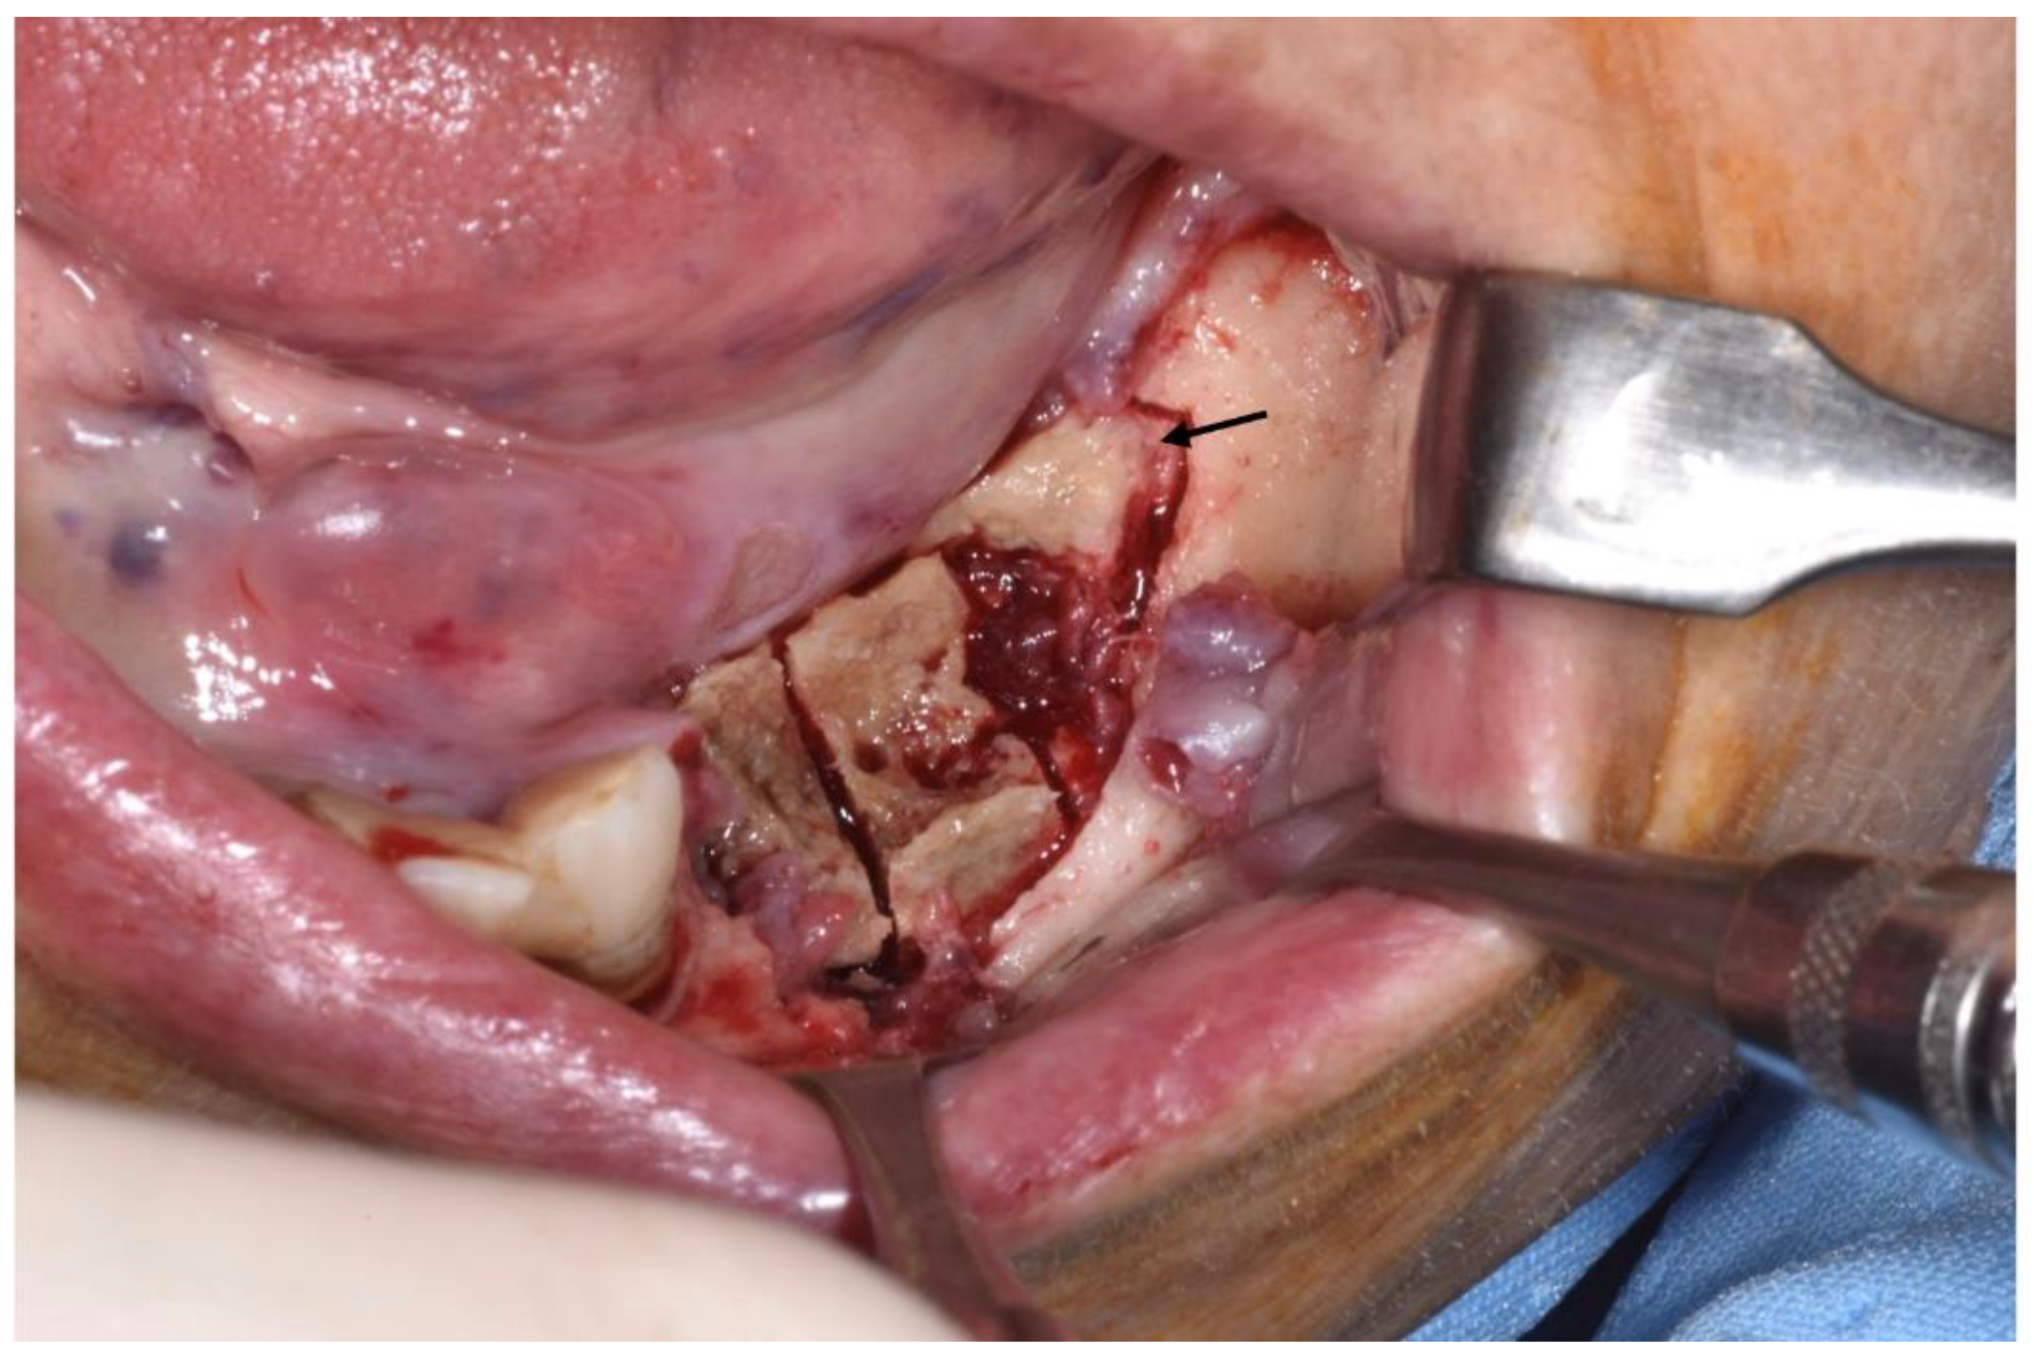

Figure 4.

Sub-marginal resection performed using piezoelectric device.

Figure 5.

Intraoperative aspect. Necrotic bone segment was observed macroscopically and cut, dividing it into three parts: a transitional zone (segment located in the mesial third of the sequestrum), totally necrotic tissue (the middle part of the segment) and healthy adjacent tissue (the distal area of the segment). The arrow schematically indicates the portion used in this case.